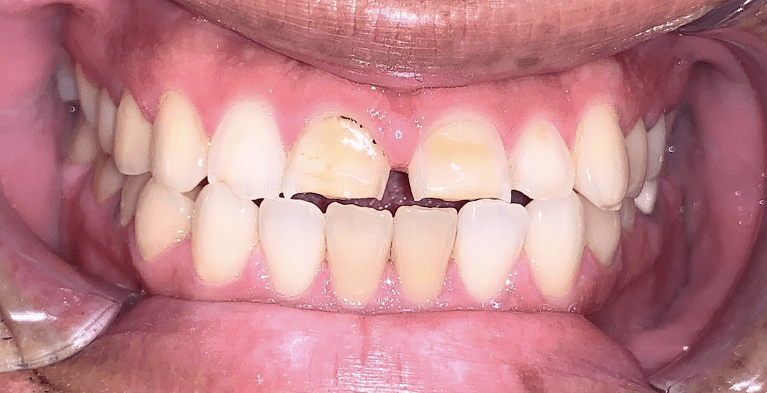

Before and after with Invisalign orthodontic treatment. Pictures taken with different phones at different setting. Used total of 27 aligners/trays. Treatment time 13.5 months